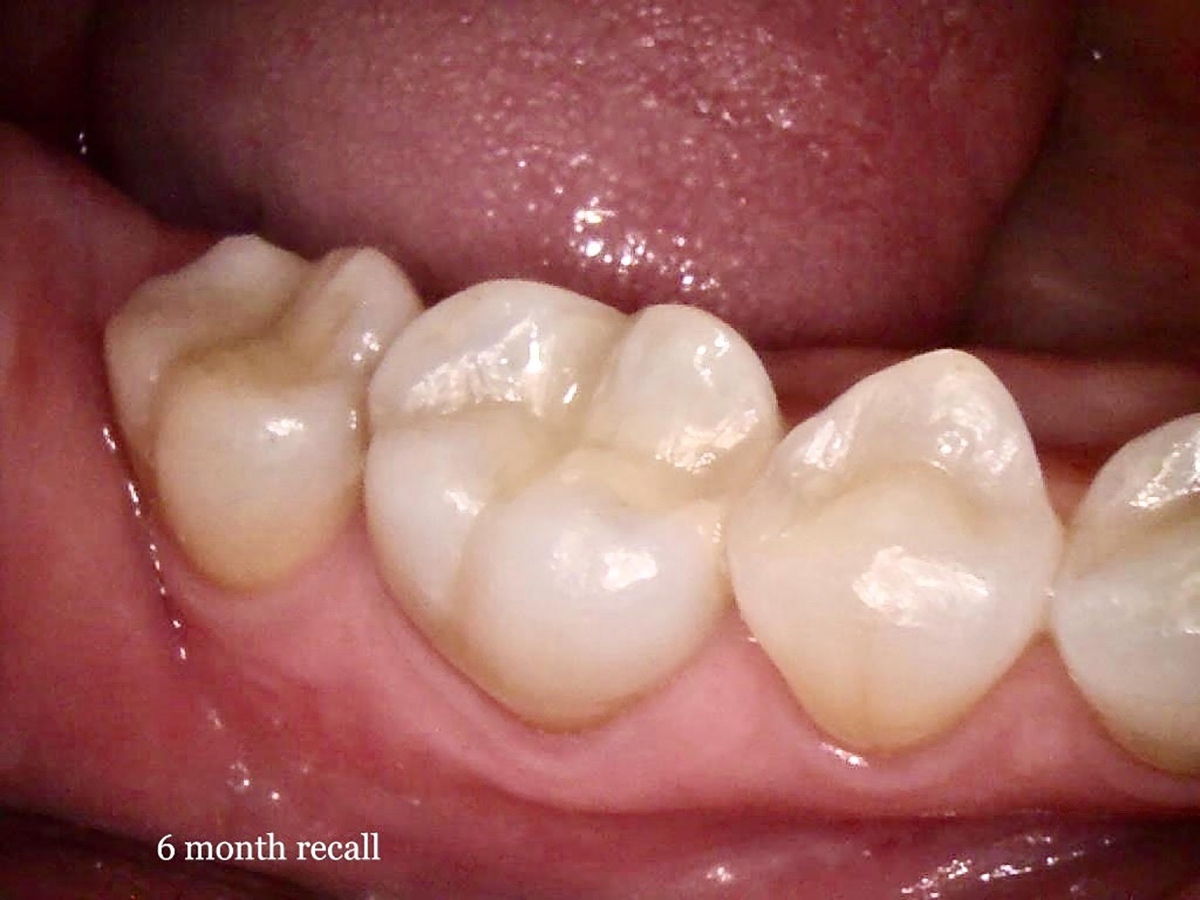

Fig 8. Six-month recall image of restoration.

Figure 8

After a clean and neat cavity preparation, liner was placed on the deep cavity surface to mask the dark amalgam stain. The liner was light-cured for 20 seconds. A wide bevel was placed on the occlusal surface, and then a ring and matrix were placed. A selective enamel etching was performed with 37% phosphoric acid (Figure 3), rinsed, and dried. Universal bond was prepared by adding one drop from each bottle of the adhesive product into a mixing well and then briefly mixing. The bond was then placed (Figure 4) and air-dried with low air for 5 seconds, then with stronger air for another 5 seconds. No light-curing was needed for this bonding system. Then, one-shade composite was placed in small increments using a condenser. Before light-curing, some occlusal anatomy was created using hand instruments, including an acorn-shaped burnisher (Figure 5) and blue titanium CIB3. The occlusal adjustments and more detailed anatomy were created using a football-shaped diamond bur and a needle-shaped diamond bur. The final finishing and polishing were done using a large, coarse disc, a fine-needle diamond bur, and white Arkansas stone. A postoperative photograph (Figure 6) showed how the restoration blended naturally with the tooth. Figure 7 and Figure 8 feature a bitewing x-ray and photograph of the tooth taken during the 6-month recall examination.

This Class II restoration demonstrated the versatility and ease of use provided by universal bonding agents. These bonding agents, such as the one used in this case, provide an all-in-one bond system that does not require light-curing, surface agitation, or a post-placement wait period.5 Universal bonding agents save time when multiple restorations in quadrant dentistry are performed. Additional activators and primers were not needed, reducing inventory cost and chairtime compared with using a non-universal bonding agent.5 A final benefit involves the reduced risk of failure in cases such as deep Class II restorations and post-and-core buildups that are difficult to reach and fully cure with light-curing.11 These agents also offer high bond strength and no postoperative sensitivity.